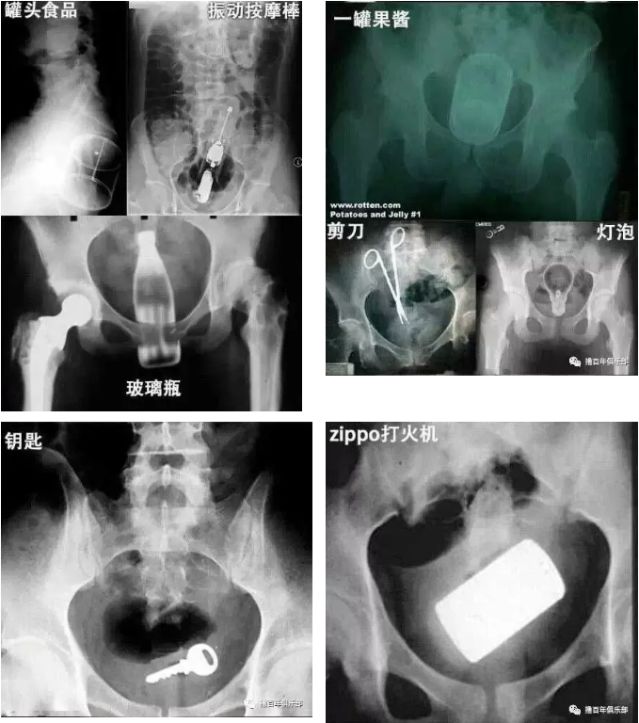

来一起看下图的x光照片吧,只有你想不到没有别人做不到的——

菊花一紧!男子洗澡摔倒,面霜棒插入肛门!进去容易出来难…